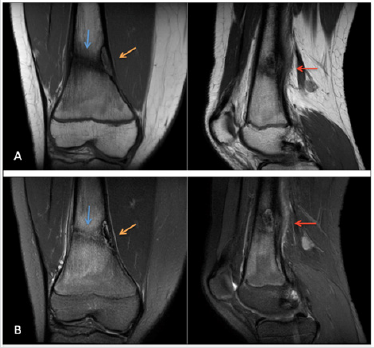

A 12 year old female patient presented to the clinic for right knee pain. She was a cross country runner and had been training for a competition. The patient described waking up in the morning to vague knee pain just above the patella and has been walking with a limp for several days. Ibuprofen has not completely controlled the pain. On exam, there was pain with weight-bearing and tenderness to palpation of the distal femur but no significantly increased pain on range of motion testing. The patient was initially sent home with conservative management. However, the patient returned with worsening pain and radiographs of the right knee were ordered. On the right knee x-ray, there was a corticallybased lucent lesion within the distal femur which most likely represented a non-ossifying fibroma (Figure 1), however, the knee joint itself appeared unremarkable. Since the finding was described as a benign lesion, the primary physician pursued the reasonable approach of conservative management for the patient. However, the patient returned again with worsening pain after continued running. A subsequent MRI was performed for further evaluation. On evaluation of the MRI, there was an unexpected healing nondisplaced fracture of the distal femur that extended into the NOF (Figure 2). Follow-up radiographs and MRI was recommended and a pediatric orthopedic surgery consultation was placed. At the consultation, the orthopedic surgeons agreed with the initial assessment of a pathologic fracture from the NOF and concluded that the fracture was healing well on its own. No further intervention was made and the patient returned to normal function after 8 weeks of rest.

Figure 2: Coronal and sagittal images of the right knee are demonstrated on the T1-weighted (Image A) and T2-weighted fatsaturated (Image B) sequences. There is a T2 hyperintense, T1 isointense cortically-based lesion with a central low signal and peripheral low signal rim at the medial-sided distal femoral metaphysis most consistent with a stage B or early stage C NOF (orange arrow). A linear band of low signal extends nearly the entirety of the femur into the NOF (blue arrow). Additionally, there is periosteal reaction and adjacent soft tissue edema consistent with a healing insufficiency fracture (red arrow).